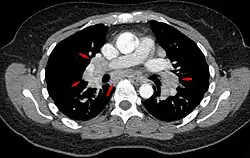

La sarcoidosis, (del griego sarx, que significa 'carne') o enfermedad de Besnier-Boeck, es una enfermedad granulomatosa sistémica, de carácter autoinmunitario, que afecta a todas las poblaciones y etnias humanas, y fundamentalmente a adultos entre 20 y 40 años. Sus causas son desconocidas. Los síntomas pueden aparecer repentinamente, pero suelen manifestarse de manera gradual. El curso de la enfermedad es variable y puede ser desde asintomática hasta crónica (en el 5 % de los casos), pudiendo llevar a la muerte (solo en un 1 % de los casos en que se hace crónica).

La enfermedad puede manifestarse en cualquier órgano del cuerpo, con mayor frecuencia en el pulmón y ganglios intratorácicos. También son frecuentes las manifestaciones oculares, cutáneas y hepáticas.

Su diagnóstico generalmente se hace por exclusión con una clínica compatible, imágenes radiológicas sugerentes y la confirmación histológica con presencia de granulomas no caseosos.